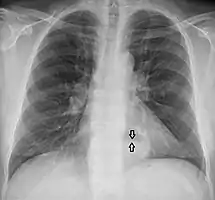

A large hiatal hernia on chest X-ray marked by open arrows in contrast to the heart borders marked by closed arrows

This hiatal hernia is mainly identified by an air-fluid level (labeled with arrows).